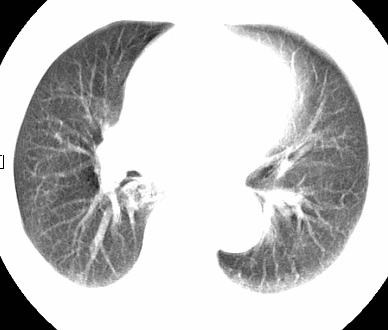

标题: CT26680:肺部右下肺静脉干结节的界定 [打印本页]

标题: CT26680:肺部右下肺静脉干结节的界定

经追查说有支扩咯血病史,但不确定

考虑1、周围型肺癌,2肺静脉畸形,前者可能大,建议增强检查。

考虑1、周围型肺癌,2肺静脉畸形,前者可能大,建议增强检查。支持!

不排除右肺下叶周围型肺癌可能。

中心型肺癌,纤支镜可帮助明确。